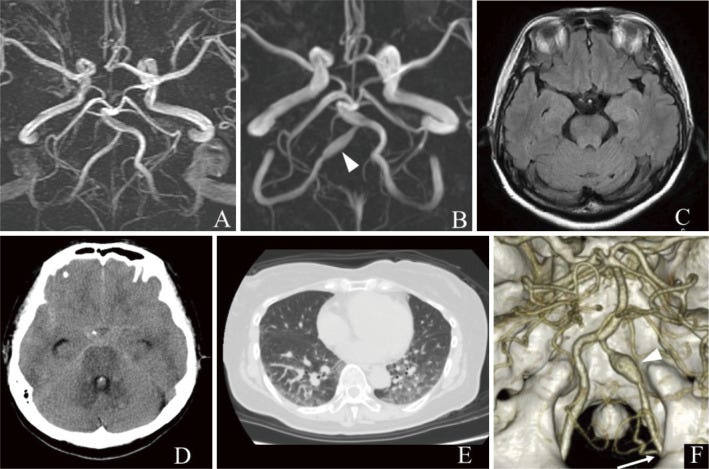

(A) Magnetic resonance angiography (MRA) performed 10 years previously shows normal right vertebral artery (VA). (B) MRA performed 3 weeks before the vaccination shows dilatation of the right VA (arrowhead). (C) Fluid-attenuated inversion recovery magnetic resonance imaging (MRI) performed on the same day shows no intracranial hemorrhage. (D) Head computed tomography (CT) performed 1 day after the vaccination shows diffuse subarachnoid hemorrhage. (E) Chest CT performed on the same day shows bilateral pulmonary effusion. (F) Three-dimensional CT angiography (3DCTA) performed on the same day shows dissecting aneurysm in the right VA (arrowhead). The right posterior inferior cerebellar artery (PICA) originated from the extradural segment of the VA (arrow).